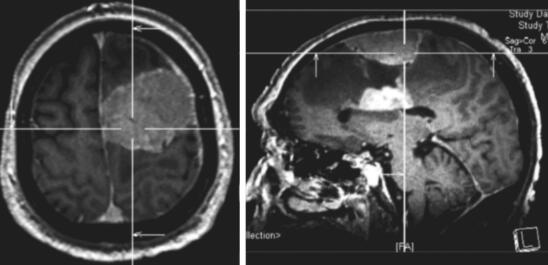

患者,男性,80岁,因“发现左额占位5年,进行性失语1月余”入院。患者于5年前体检时发现左额占位(图1),T1等信号T2等信号,未进一步行增强检查。患者外院就诊考虑患者脑膜瘤可能大,结合患者年龄建议保守治疗密切随访。患者之后未定期就诊复查头颅MRI。患者自1个月前开始出现言语迟缓,主要表现为言语表达困难,无言语理解障碍,进行性加重,伴右侧肢体肌力进行性减退,左侧肢体肌力未受影响。患者就诊外院后进一步查头颅MRI提示左额多发病灶,浅部病灶明显均匀强化,考虑患者既往病史考虑脑膜瘤可能大;深部病灶不均匀强化,伴坏死,高级别胶质瘤不能除外(图2)。患者进一步查头颅FDG-PET提示左额浅部病灶放射性摄取值轻度增高,SUV值最大8.9,结合病史,考虑颅内原发低代谢肿瘤(脑膜瘤可能大);左额深部侧脑室上方病灶放射性摄取异常增高,SUV最大值21.6,考虑脑内原发恶性肿瘤可能大,体部PET显像未见FDG代谢明显异常增高(图27-3)。患者入院后积极完善相关检查,排除手术禁忌后行左额浅部病灶切除+深部病灶活检术,术中冷冻结果提示左额浅部病灶为脑膜瘤,深部病灶为小圆细胞恶性肿瘤。

随着年龄的增加,恶性胶质瘤的发病率也增加,一半以上的恶性胶质瘤患者年龄大于65周岁。而恶性胶质瘤中,以胶质母细胞瘤(WHO Ⅳ)最为常见。胶质母细胞瘤患者根据肿瘤部位和大小的不同,临床表现差异较大。部分患者无症状或者通常表现为记忆力减退、轻度头晕及乏力等症状,部分功能区胶质瘤患者还可以表现为一侧肢体肌力减退或者失语等相应功能缺损表现,癫痫症状较低级别胶质瘤少见。部分肿瘤发生出现出血卒中时可以表现为急性剧烈头痛等脑出血表现。在CT上根据肿瘤实质性情况的不同,高级别胶质瘤可表现为低密或者等密度病灶。在MR影像上通常表现为T1等或者低信号,T2高信号,而根据肿瘤血-脑脊液屏障破坏程度的不同,肿瘤通常可以表现为不规则或者花环状强化,伴有坏死和囊变,边界不清,瘤周水肿较少见。在FDG-PET中高级别胶质瘤通常表现为放射性物质的异常高摄取,但是FDG-PET通常不能用来鉴别诊断恶性程度相近的脑转移瘤和恶性胶质瘤。该患者老年男性,临床上逐渐出现失语及功能障碍等症状,额叶深部病灶在MRI成不均匀明显强化,并且FDG-PET显示为颅内原发的恶性肿瘤(图3),因此恶性胶质瘤可能依然大,需要进一步病理明确。

图3 患者头FDG-PET提示左额浅部病灶放射性摄取值轻度增高,SUV值最大8.9(A),左额深部侧脑室上方病灶放射性摄取异常增高,SUV最大值21.6(B)